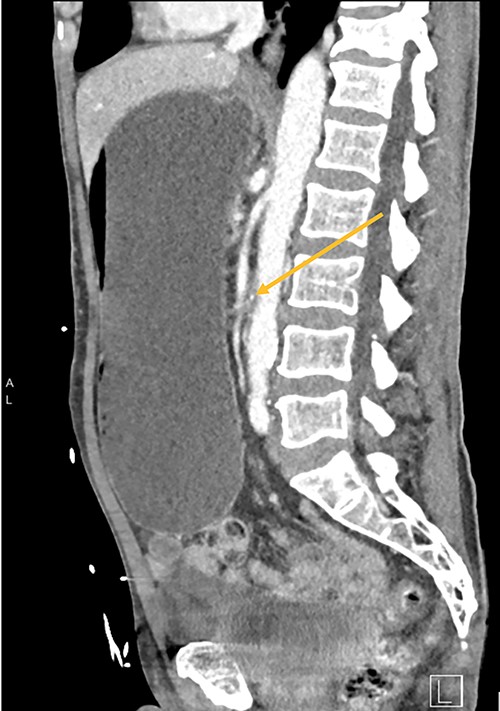

A 73-year-old male was transferred from a private hospital to the local public hospital 5 days post left total hip replacement with a 2-day history of nausea, bilious vomiting and colicky abdominal pain. His bowels had not opened since prior to the procedure. His background included previous right total hip replacement, benign prostate hyperplasia and depression. His medications included mirtazapine, tamsulosin, calcium carbonate and denosumab. He is a non-smoker and does not drink alcohol. On examination his observations were all within normal limits and he appeared to be very slim build. His height was 174 cm and he weighed 49 kg with a body mass index of 16.2. His abdomen was generally tender and distended, but not peritonitic. His blood results showed a serum potassium of 3.2 mmol/L, sodium 148 mmol/L, magnesium 0.94 mmol/L, albumin 34 g/L, creatinine 104 μmol/L, eGFR 61 ml/min (acute kidney injury), white cell count 7.7 × 109/L, haemoglobin 114 g/L. A computed tomography (CT) scan of his abdomen (Figs 1–3) showed a grossly distended stomach measuring 26.2 cm × 14.3 cm × 14.6 cm. It appeared fluid filled with moderate distension of the first and second part of the duodenum. The third part of the duodenum was partly fluid filled with an abrupt luminal collapse within the distal aspect where it passes between the superior mesenteric artery and aorta. The aorta mesenteric angle was reduced to ~23°. The remaining small bowel was decompressed with no free fluid or gas.

CT shows duodenum obstructed (orange arrow) between the aorta and superior mesenteric artery.